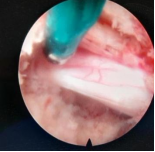

4.微创脊柱内镜技术:PELD+UBE+OSE

脊柱内镜技术是一项开展较早的脊柱外科微创技术,与传统开放手术相比,它是借助天然解剖间隙建立微创工作通道,解除神经压迫;对椎旁肌肉损伤较小,且能够最大程度地保留完整的脊柱结构,维持了术后脊柱的稳定,具有创伤小、出血少、恢复快、并发症少、疗效确切等优点。目前已开展椎间孔镜下髓核摘除术,单侧双通道脊柱内镜(UBE)下椎管减压术并处于区域内领先水平。性爱视频

在江苏省内率先开展了单孔分体式脊柱内镜技术(OSE),处国内领先水平。

单孔孔镜

单侧双通道技术

单孔分体式内镜下腰椎固定融合技术